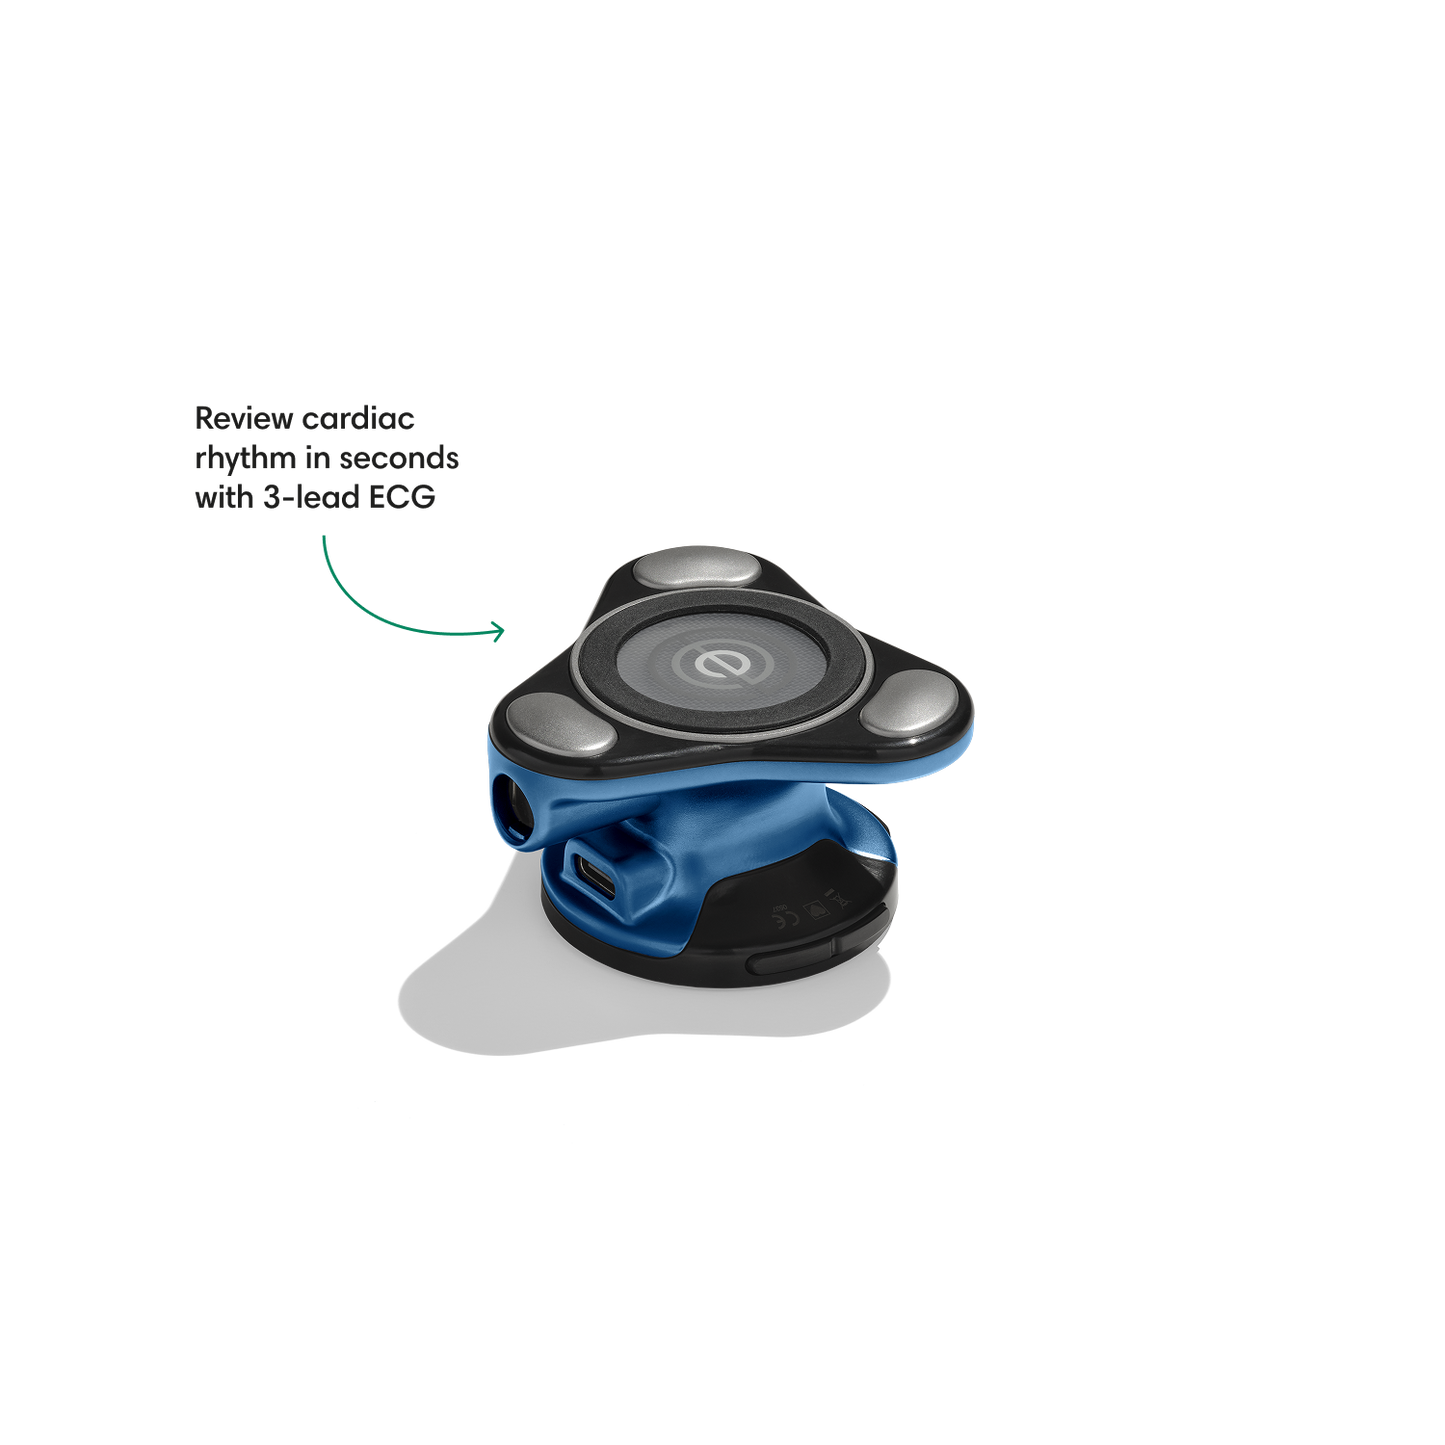

Go beyond sound alone.

For the first time ever, measure heart rate, visualize 3-lead ECG, and see detection results — right on a built-in, full-color display.